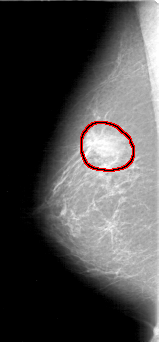

D_4070_1.RIGHT_MLO

FILE: D_4070_1.RIGHT_MLO.OVERLAY

TOTAL_ABNORMALITIES 1

ABNORMALITY 1

LESION_TYPE MASS SHAPE OVAL MARGINS OBSCURED

ASSESSMENT 0

SUBTLETY 4

PATHOLOGY BENIGN

TOTAL_OUTLINES 1

BOUNDARY